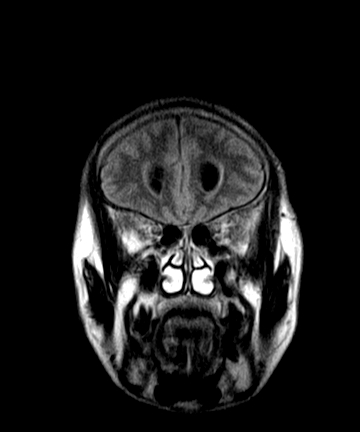

标题: MRI2064:少见病例。男性52,视力下降多年。 [打印本页]

标题: MRI2064:少见病例。男性52,视力下降多年。

四脑室区见混杂信号占位影,脑室系统扩张明显,临近结构显著受压称位,患者52岁,多考虑室管膜瘤可能性大

考虑第四脑室室管膜瘤并梗阻性脑积水;部分性空蝶鞍;左侧上颌窦粘膜下囊肿。

考虑第四脑室室管膜瘤【血供丰富血管母细胞瘤可能】并梗阻性脑积水;部分性空蝶鞍;左侧上颌窦粘膜下囊肿。

小脑蚓部胶质脑膜瘤突入四脑室;肿瘤内见血管流空信号和钙化信号.

比较典型的脉络丛乳头状瘤并脑积水,鉴别小脑蚓部血管母细胞瘤。